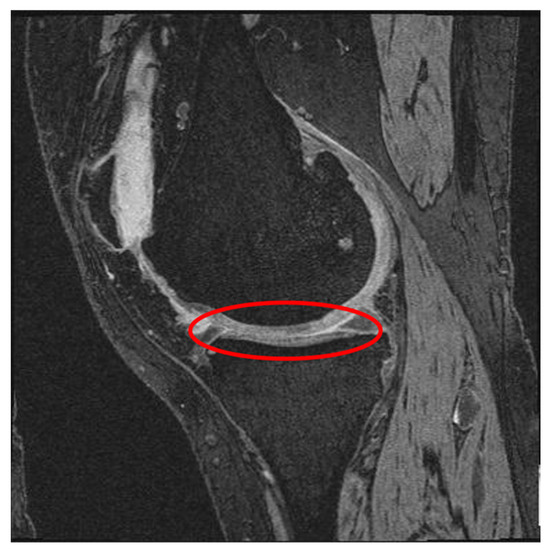

We cropped each image as a preprocessing step that helps to keep the cartilage region while removing regions that are less informative for knee OA classification. We cropped the image (original size 384 × 384) from the center using both square and rectangular regions. An example of cropping a knee MR image to various sizes is provided in Figure 3. Through various tests we discovered that the window size of 160 × 160 achieved the highest F-measure.

Figure 3. A full 384 × 384 image and the results of cropping to various window sizes.